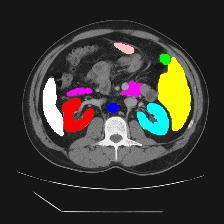

Medical image segmentation is one of the most fundamental tasks concerning medical information analysis. Various solutions have been proposed so far, including many deep learning-based techniques, such as U-Net, FC-DenseNet, etc. However, high-precision medical image segmentation remains a highly challenging task due to the existence of inherent magnification and distortion in medical images as well as the presence of lesions with similar density to normal tissues. In this paper, we propose TFCNs (Transformers for Fully Convolutional denseNets) to tackle the problem by introducing ResLinear-Transformer (RL-Transformer) and Convolutional Linear Attention Block (CLAB) to FC-DenseNet. TFCNs is not only able to utilize more latent information from the CT images for feature extraction, but also can capture and disseminate semantic features and filter non-semantic features more effectively through the CLAB module. Our experimental results show that TFCNs can achieve state-of-the-art performance with dice scores of 83.72\% on the Synapse dataset. In addition, we evaluate the robustness of TFCNs for lesion area effects on the COVID-19 public datasets. The Python code will be made publicly available on https://github.com/HUANGLIZI/TFCNs.

翻译:医学图像分解是医学信息分析的最根本任务之一,到目前为止已经提出了各种解决办法,包括许多深层次的学习技术,如U-Net、FC-DenseNet等。 然而,高精度医学图像分解由于医疗图像中存在固有的放大和扭曲,以及存在与正常组织密度相似的损伤,因此仍是一项极具挑战性的任务。在本文件中,我们建议TFCN(全面革命稠密网络的传输者)通过向FC-DenseNet引进ResLear-Transerferent(R-Transerfor)和Culvacial线性关注区(CLAB)来解决这一问题。TFCN不仅能够利用CT图像中更多的潜在信息来提取特征,而且还能够通过CLAB模块更有效地捕捉和传播语性特征和过滤非神经性特征。我们的实验结果表明,TFCN可以在Syapseion/SymblyDDS上以83CN-72 ⁇ 的分数实现状态。此外,我们在Synapse-DRIS数据设置上,我们还将评估CUTFTFI/LIS的可靠度。